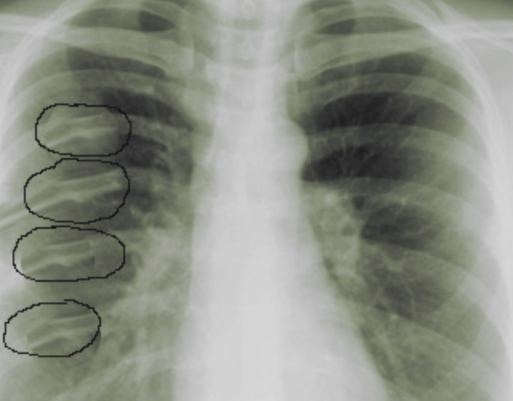

Un exemple de fractures de côtes objectivées par radiographie:

• Les fractures de côtes sont habituellement liées à une lésion directe de la paroi thoracique, souvent consécutive à un choc violent (ex : par décélération très rapide ou par coup de batte de base-ball ou par chute). Cependant, parfois, chez les patients âgés, un traumatisme léger ou modéré (ex : une chute sans gravité) peut suffire. Si ≥ 3 côtes adjacentes se fracturent au niveau de 2 sites distincts, le segment fracturé provoque la formation d’un volet costal (= multiples fractures de ≥ 3 côtes adjacentes qui se traduisent par un segment de la paroi thoracique séparé du reste de la cage thoracique : c’est un marqueur de blessure du poumon sous-jacent).